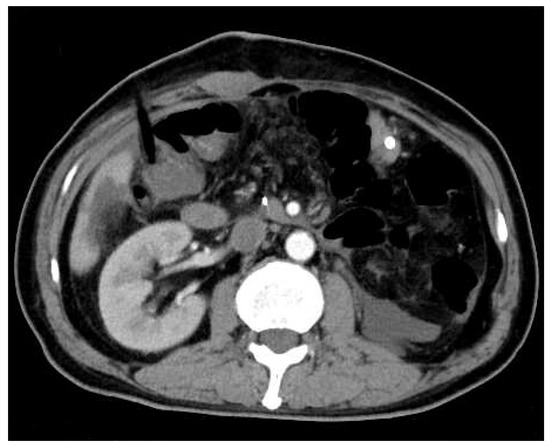

Enhanced upper abdominal computed tomography (CT) performed in the local hospital indicated ampullary mass. (A): plain scan phase; (B): arterial phase; (C): venous phase; (D): delayed phase. A 59-year-old male patient was hospitalized for “recurrent hematochezia for 8 days”. Enhanced upper abdominal computed tomography (CT), performed in the local hospital, indicated ampullary mass. On CT, the tumor showed uneven enhancement in the arterial phase, but the enhancement significantly weakened in the venous phase and delayed phase. Therefore, this imaging feature was significantly different from that in the primary ampullary tumor or pancreatic tumor. Duodenoscopy revealed duodenal papilla hemorrhage. Urinalysis showed no hematuria. After conservative treatment, the hemorrhage was not resolved. Then, the patient was transferred to our hospital for further treatment. He had received radical nephrectomy due to clear cell renal cell carcinoma (ccRCC) of the left kidney 16 years ago. The CT scan mentioned above revealed that his right kidney was normal. On admission, his laboratory tests results were as follows: leukocyte count of 3.9 × 109/L; neutrophilic granulocytes percentage of 75%; C-reactive protein of 1.6 mg/L; hemoglobin of 102 g/L; total bilirubin concentration of 12.6 μmol/L; alanine aminotransferase of 16 U/L; aspartate aminotransferase of 19 U/L.